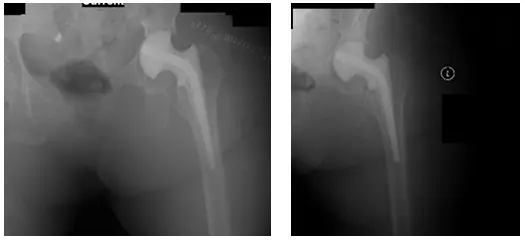

Patient is a 68 year old male who came in 2010 by referral from another orthopedic surgeon. Patient complained of left hip pain that he stated had been bothering him for the past two years.

Patient had mentioned that he was hospitalized one year ago with a septic hip. When at the hospital, the patient had drainage, irrigation and debridement, and a needle aspiration of the left hip, which revealed that he had MRSA from a previous cervical and lumbar spine surgery done at an outside institution. Patient had come in with X-rays to review

X-rays reveal chronic arthritis of the left hip, which ispostinfectious

Also seen is shrinkage/resorption/absence of the left femoral head. X-rays also partially show fusion at L3-L4 and L4-L5.

X-Rays taken the day of surgery. X-rays show a Left Antibiotic Spacer

X-Rays show revision left hip prosthesis post-operative